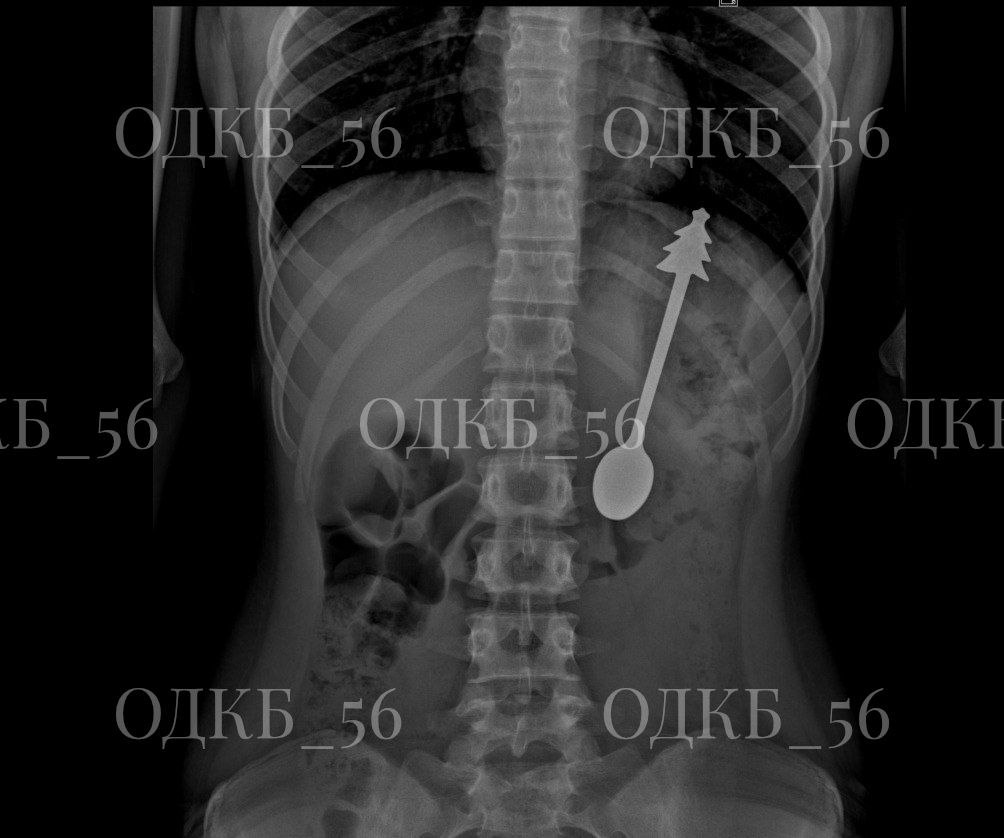

В областную детскую больницу привезли мальчика, который случайно проглотил металлическую ложку. Врачи сразу сделали рентген. Снимки показали, что в желудке находится ложка длиной 14 см. Ребенка срочно перевели в хирургическое отделение. Операцию провели под общим наркозом. Инородный предмет аккуратно достали с помощью эндоскопа. Метод безопасный и не требует разрезов. После операции ребёнок чувствовал себя хорошо. Уже на следующий день его отпустили домой.